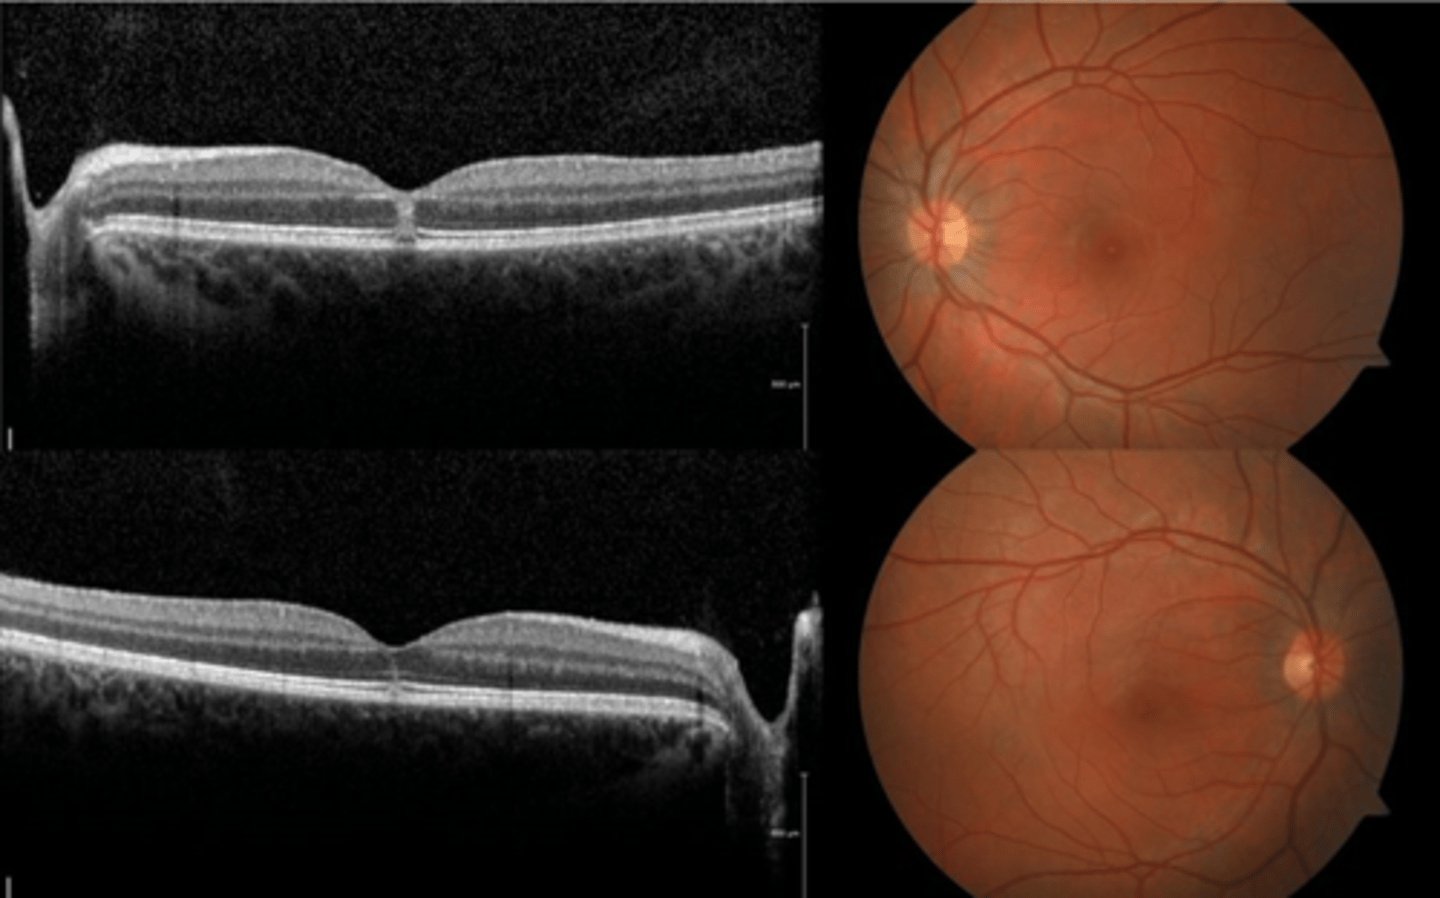

How does choroidal rupture appear on OCT here?

loss of RPE continuity at site of rupture = inner choroid atrophy

How does choroidal rupture appear on OCT here?

RPE disruption

+/- hemorrhage